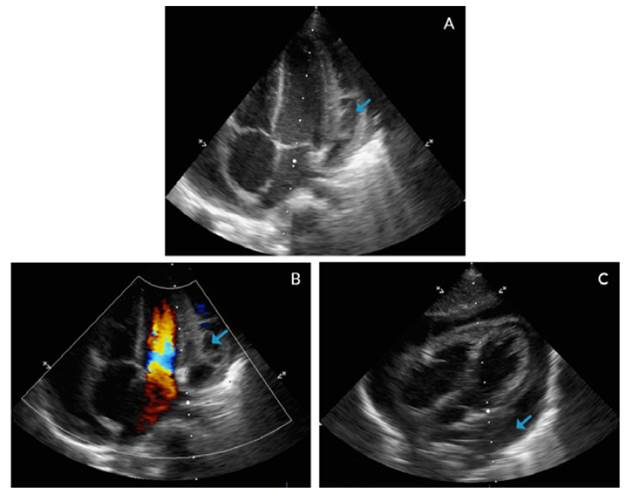

In addition, an echocardiogram showed global pericardial effusion and the presence of thick membranes between the visceral and parietal pericardium, without signs of cardiac tamponade, adequate ventricular function, ventricular ejection fraction of 77% and central venous pressure of 8-10mmHg, without signs of pulmonary hypertension (Figure 3).

The echocardiogram is the diagnostic method of choice to clarify radiological findings. 2,3 In this case, it showed a global pericardial effusion associated with the presence of thick membranes between the visceral and parietal pericardium, without cardiac tamponade, systolic-diastolic function involvement or alterations in the myocardium. Computed tomography (CT) is indicated when emergency echocardiogram is not available and when inconclusive echocardiographic results, poor response to treatment, atypical presentation, penetrating lesion, suspicion of neoplasms and pulmonary infections or mediastinitis are observed. 13 This patient did not require chest CT because of his rapid improvement, which reduced the possibility of complications.